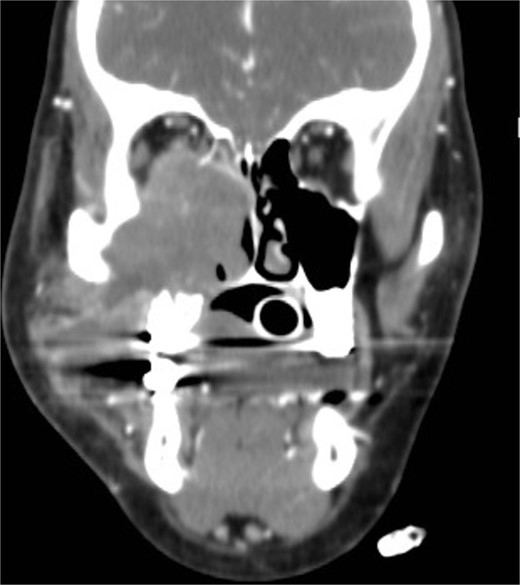

Coronal NCCT image of the paranasal sinuses showing isolated destructive right maxillary sinus lesion violating the right orbit.

An 18-year-old adolescent mentally challenged male was complaining of chronic right thick purulent nasal discharge, cough, and headache, which did not respond to multiple courses of oral antibiotics. Purulent discharge was seen filling the right nasal cavity and the nasopharynx during endoscopic examination. NCCT images (Fig. 7) revealed a destructive right maxillary sinus lesion. The patient underwent endoscopic sinus surgery, intra-operative frozen section showed granuloma, right medial maxillectomy with removal of the invasive fungal granuloma was performed (Fig. 8), and tissue cultures revealed Aspergillus flavus. Infectious disease team was involved, and the patient was started on a 6-months course of oral antifungal agent. The patient remained symptomless throughout his 1 year regular appointments.